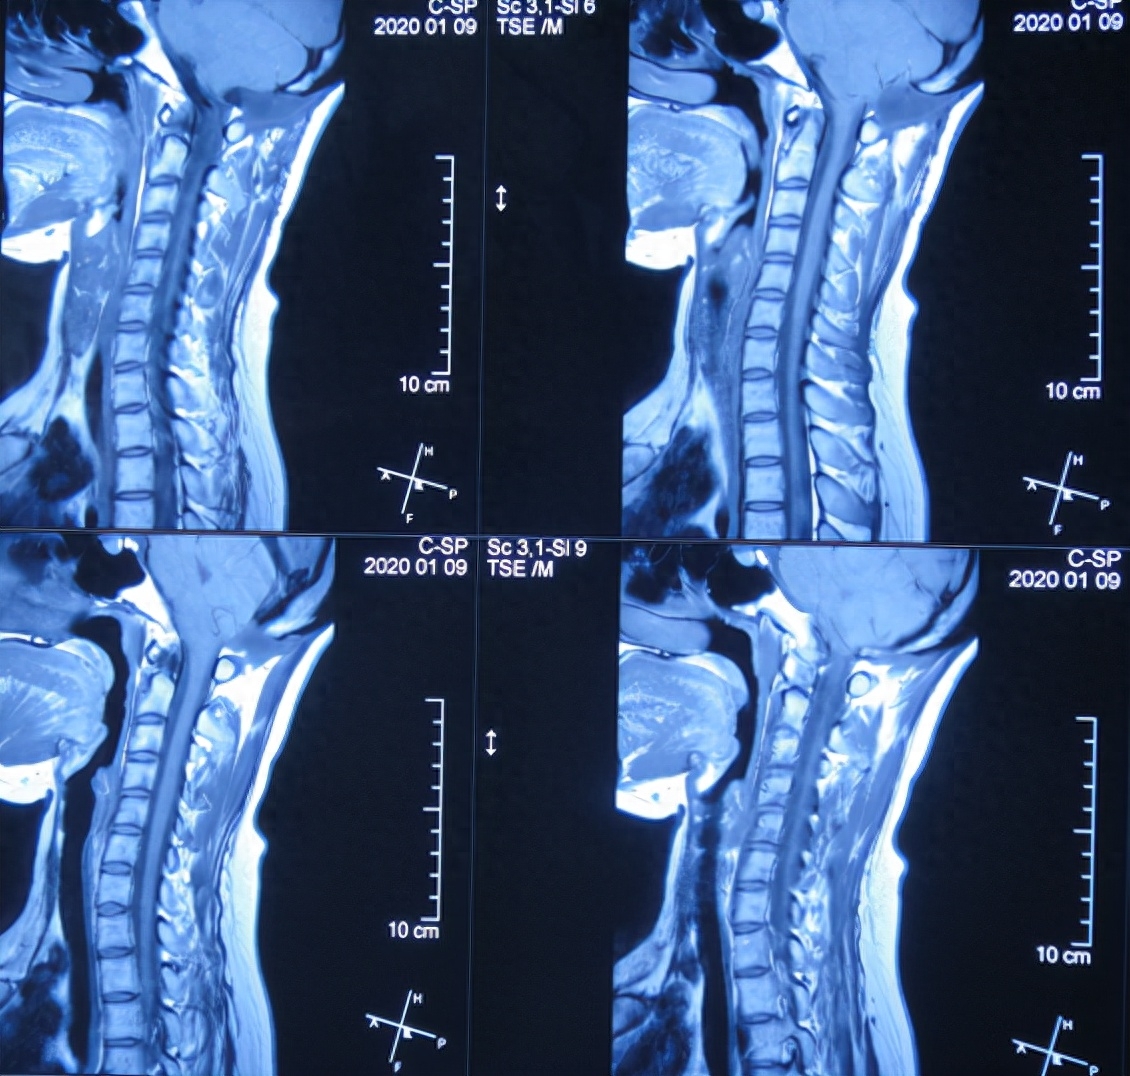

出院后8个月即2020年1月9日,来院复查。复查时:身体完全正常(图-19),查颈椎核磁:无异常(图-20)。

图-20:2020年1月9日颈部核磁